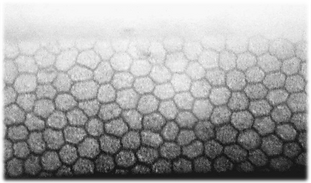

CONTEO

ENDOTELIAL

Un microscópio especular permite evaluar las células del endotelio corneal, que es la capa más interna de la córnea (la parte transparente del ojo).

Estas células son muy importantes porque mantienen la córnea clara y sin exceso de líquido.